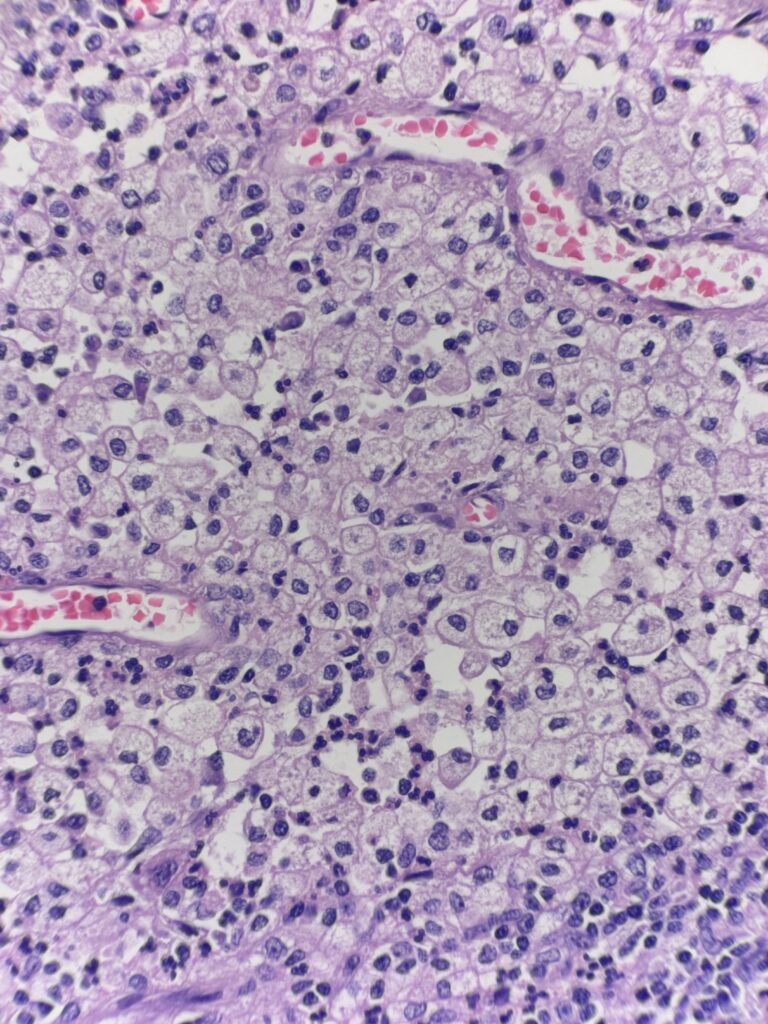

History: 44 y/o female presents with biliary colic and undergoes a cholecystectomy

Diagnosis: Xanthogranulomatous cholecystitis

The first image shows gallbladder mucosa with chronic inflammation and reactive epithelial changes. The following images show regions deeper in the submucosa and muscularis consisting of nodular aggregates of foamy histiocytes. These cells are positive for CD68 and negative for pankeratin – to differentiate this inflammatory entity from an infiltrating carcinoma.